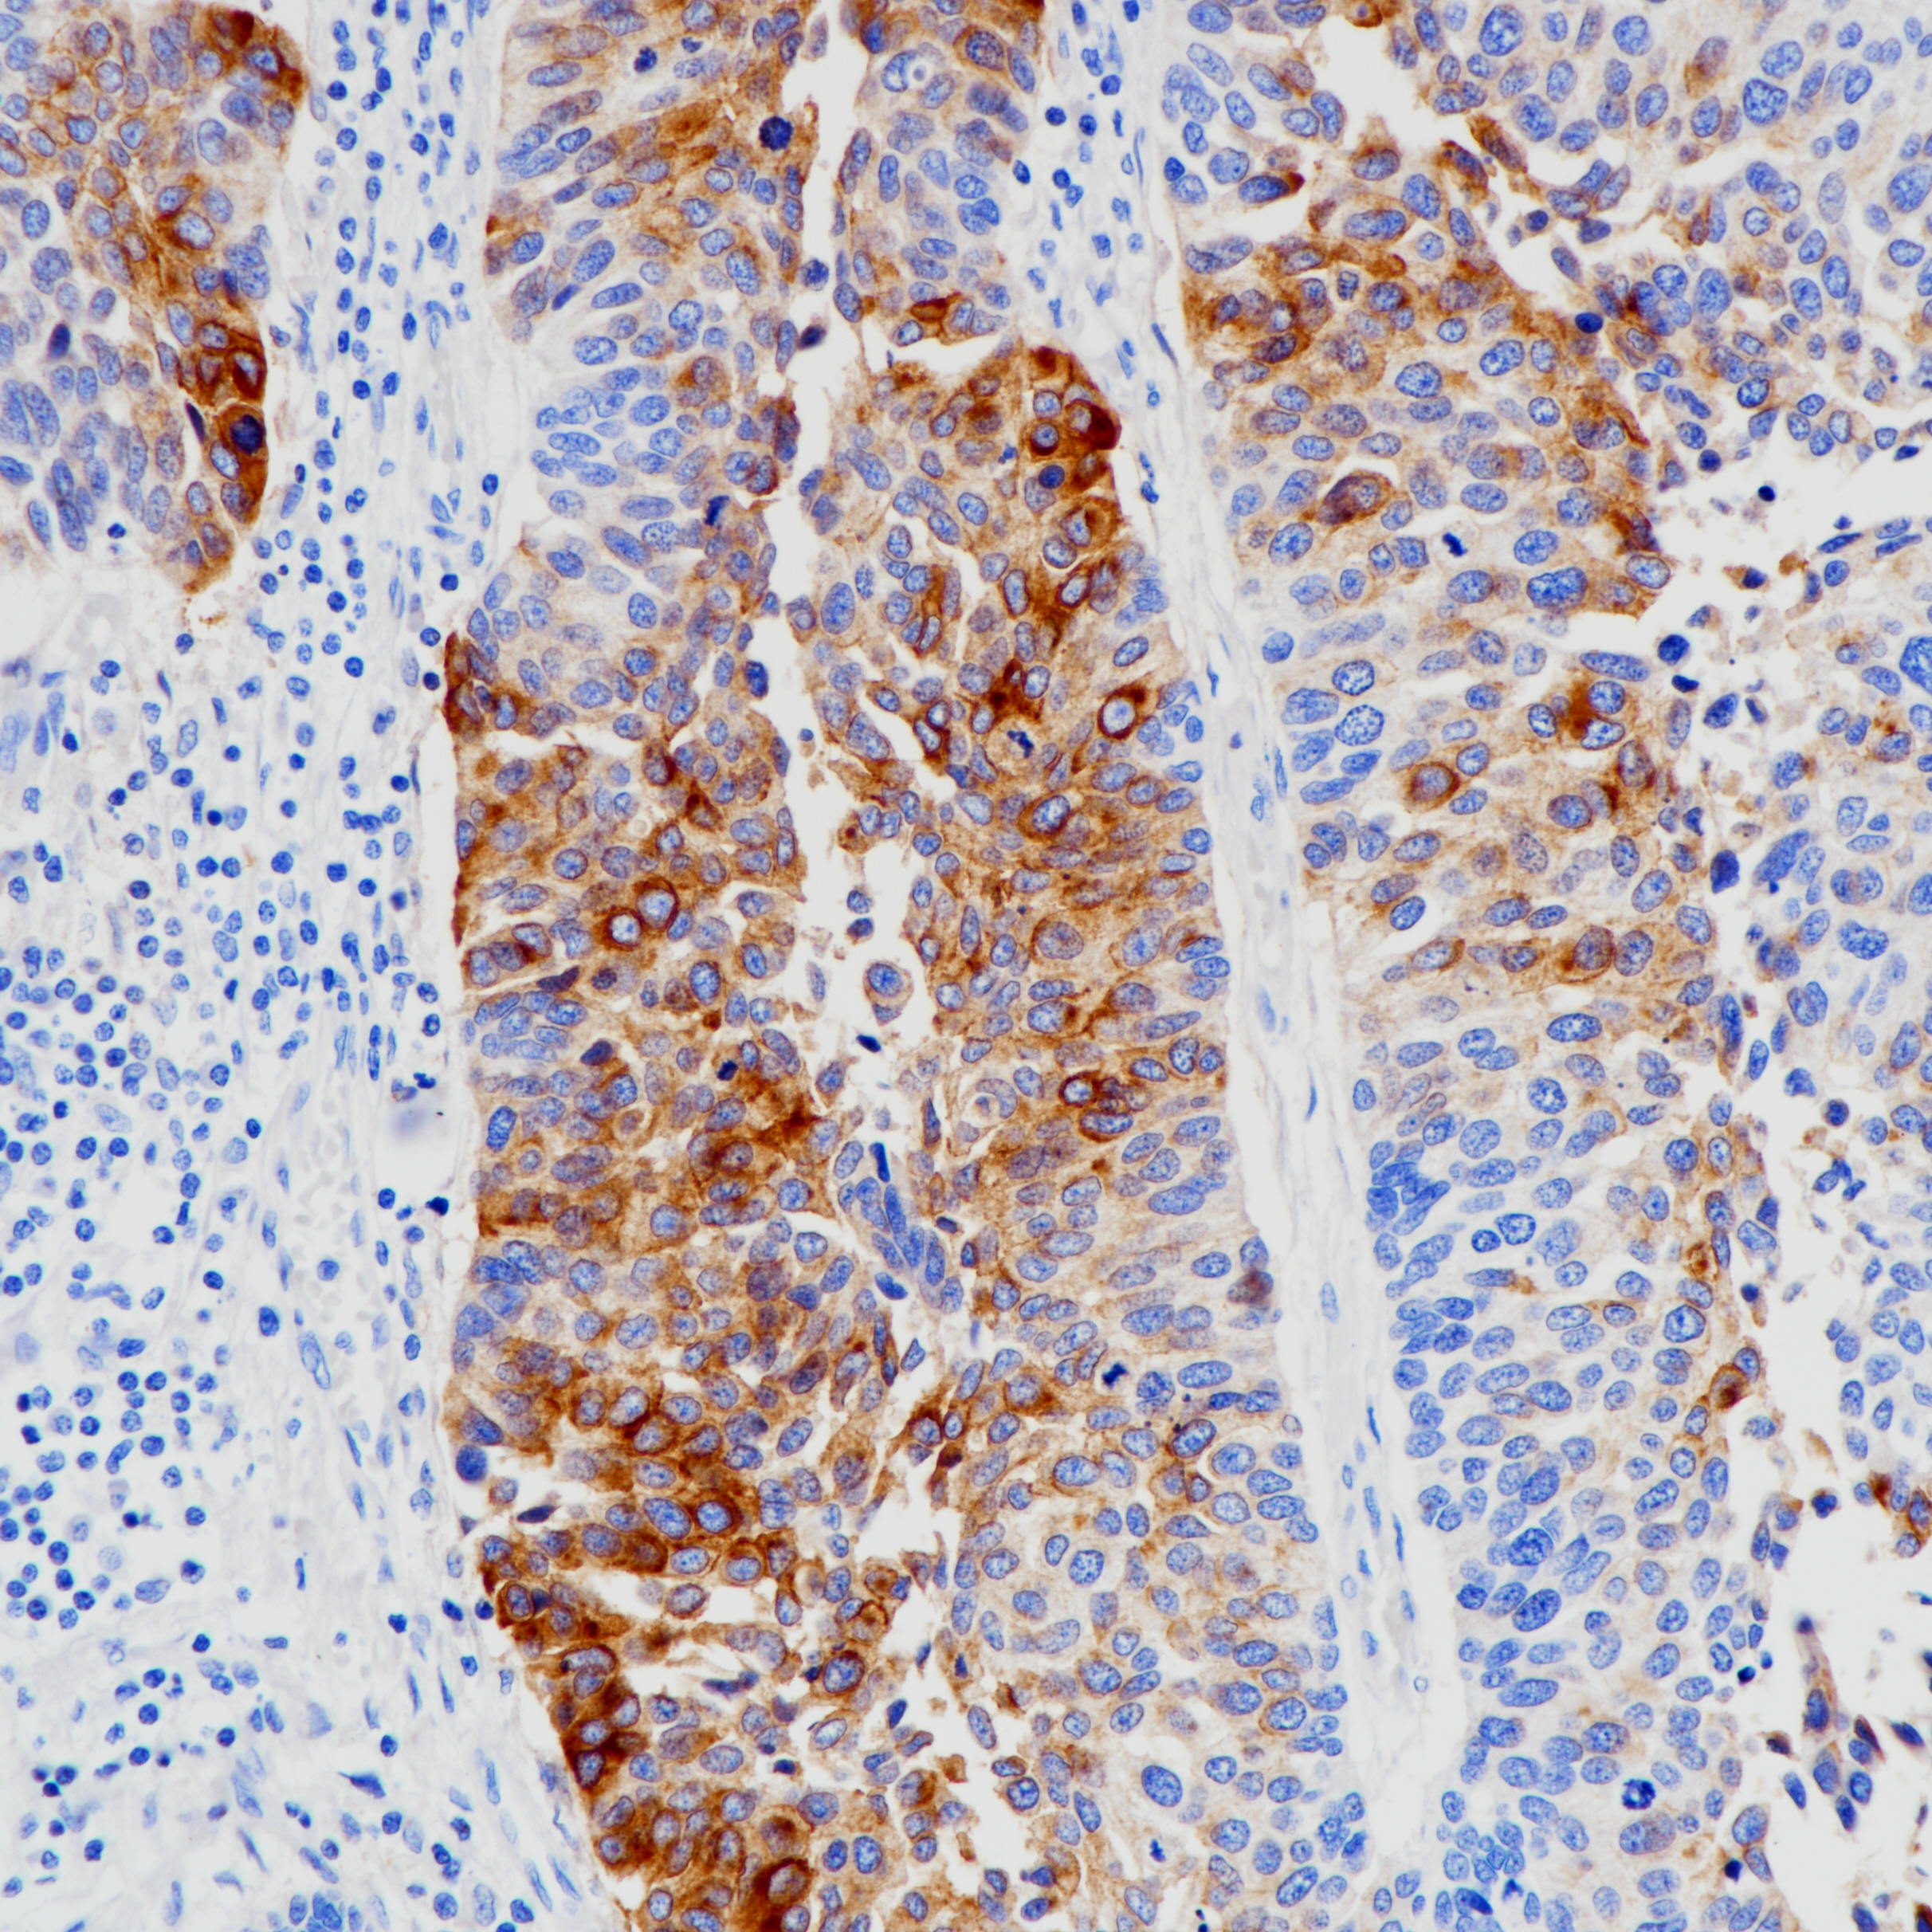

1. Olaf K , Jan V , Manfred D . Uroplakin III is a highly specific and moderately sensitive immunohistochemical marker for primary and metastatic urothelial carcinomas.[J]. American Journal of Clinical Pathology, 2000(5):683.

2. Parker D C , Folpe A L , Bell J , et al. Potential utility of uroplakin III, thrombomodulin, high molecular weight cytokeratin, and cytokeratin 20 in noninvasive, invasive, and metastatic urothelial (transitional cell) carcinomas.[J]. American Journal of Surgical Pathology, 2003, 27(1):1-10.

3. Koga F , Kawakami S , Fujii Y , et al. Impaired p63 Expression Associates with Poor Prognosis and Uroplakin III Expression in Invasive Urothelial Carcinoma of the Bladder[J]. Clinical Cancer Research An Official Journal of the American Association for Cancer Research, 2003, 9(15):5501-7.